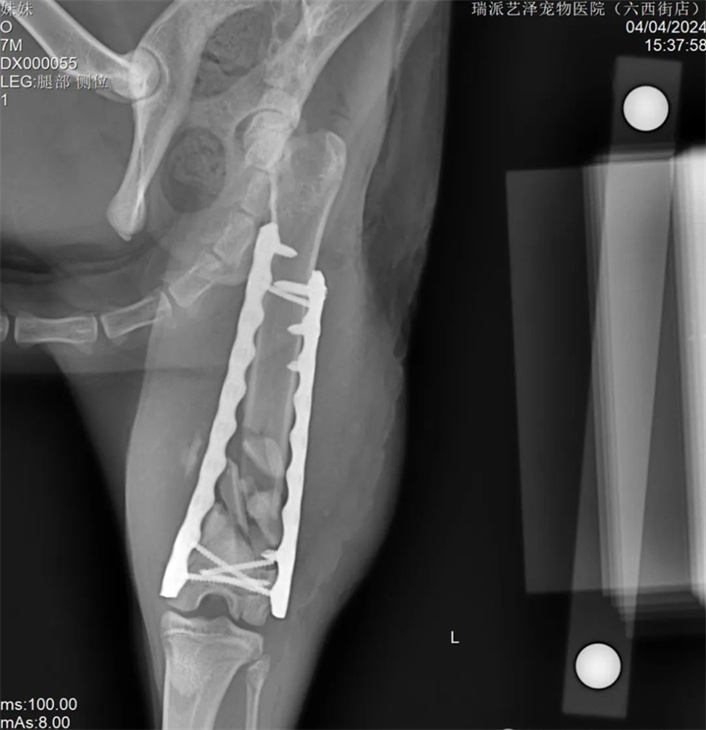

意外事故時有發生,導致各種災難性的後果。有時我們可以救治,但很多時候我們卻無能為力。這隻貓從高處跳下,遭受了嚴重的粉碎性骨折。手術的困難在於:幼貓需要考慮股骨的生長問題。幸運的是,6個月以上年齡的貓,股骨遠端生長板已經沒有太多剩餘的生長空間。其次,也要考慮動物術後無法有效限制運動,這涉及到股骨遠端髕股滑車和膝關節的活動。所採用的固定結構要考慮生長、機械穩定性和骨癒合等因素。基於上述考慮,股骨遠端採用內外雙板固定,既穩定又能中和骨骼的軸向壓縮力。 PRCL-6.5+5mm 骨板 內外固定採用股骨乾螺絲固定。採用膝關節外側入路,延伸至股骨中部。先行股骨內側固定,內側骨板不需過多塑形,再進行外側固定。在結構和力學穩定的情況下,盡量少用螺絲,盡量採用鎖定螺絲固定。術後需加強活動,避免肌肉沾黏及股四頭肌收縮。術後可使用預防性90-90繃帶固定3-5天。

手術後追蹤及複查一切正常。